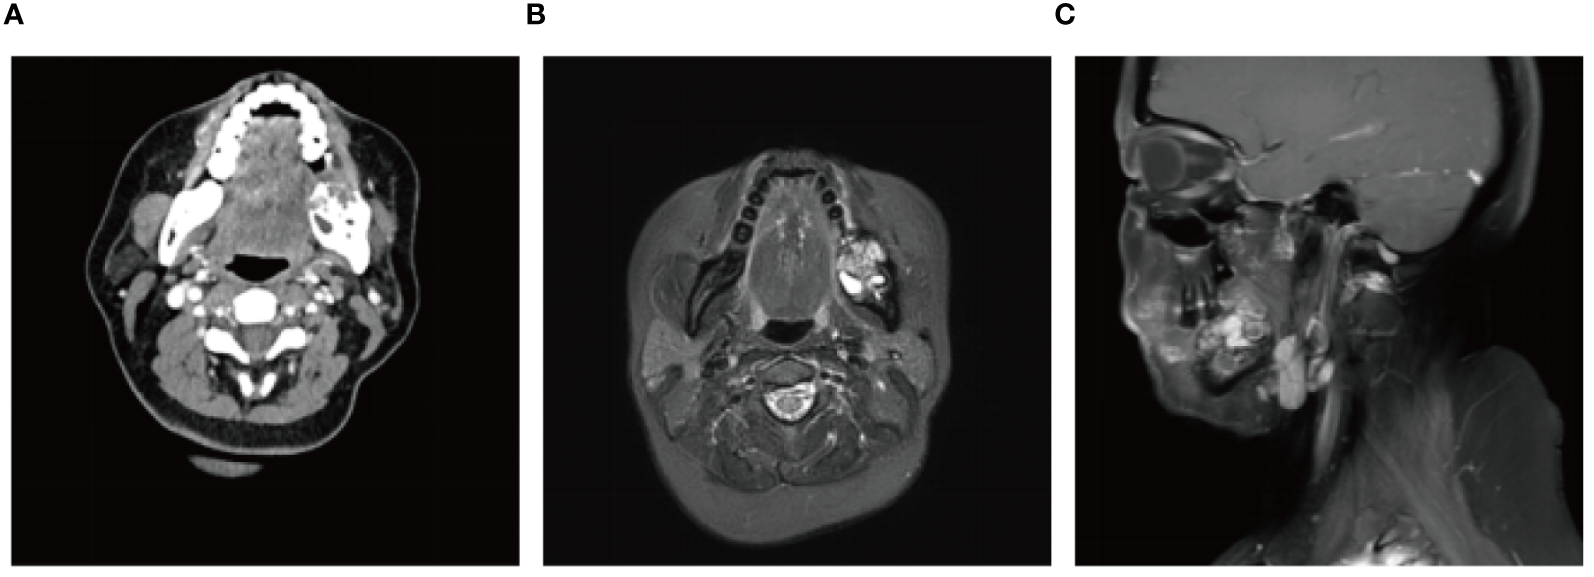

A 56-year-old female underwent surgery for ameloblastoma in the left mandible 2 years previously. Specialist examination revealed that the patient had swelling on the left face and neoplasm in the area surrounding the left mandibular angle and ramus, approximately 5.0 × 4.0 cm measuring in size. The patient also had a mild limitation in mouth opening, and 36, 37, and 38 were not detected in the oral cavity. According to the patient’s previous medical records and consultation report from the pathology department of our hospital, the pathological diagnosis of the patient was confirmed as ameloblastoma (Figure 1). The patient was diagnosed with ameloblastoma upon admission and scheduled to undergo partial mandibular resection and fibular osteocutaneous flap repair. She underwent CTA examination of the maxillofacial and the left calf prior to surgery. The obtained CTA data were imported into a software workstation for 3D reconstruction and subsequently downloaded onto a holographic display (Figures 2, 3). During the operation, the left calf was automatically positioned according to the holographic display, and the perforator vessels were dissected in real-time (Figure 4). Fibular osteocutaneous flaps were prepared to repair the mandible, and direct sutures were placed at the donor site (Figures 5, 6). After the operation, the flap fully survived, and during the 6-month follow-up, the patient expressed satisfaction with the reconstructive outcome.

Figure 1

Preoperative maxillofacial imaging. (A) Cross-section plane of the preoperative computed tomography scan; (B) Cross-section plane of preoperative magnetic resonance; (C) Coronal plane of preoperative magnetic resonance.